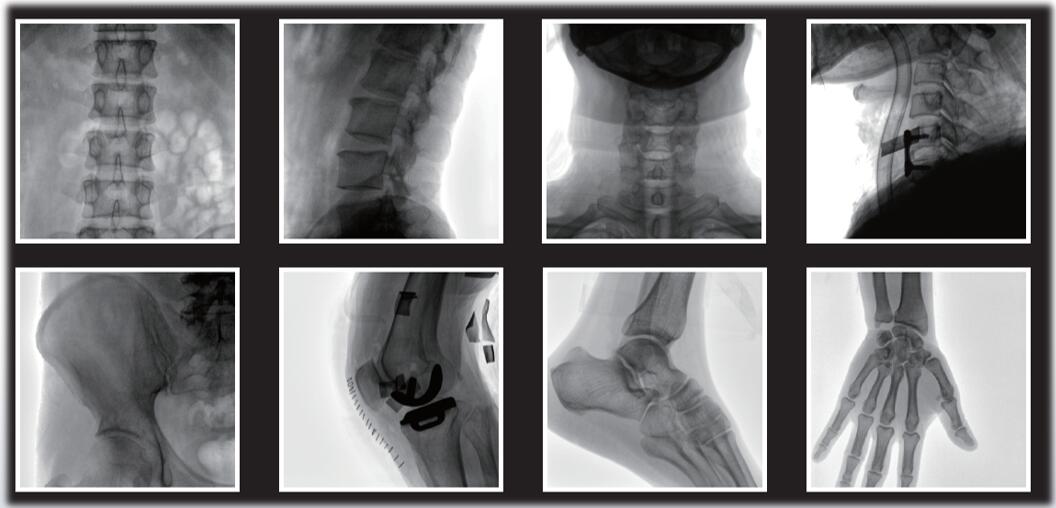

大尺寸動(dòng)態(tài)平板探測(cè)器,圖像清晰細(xì)膩,滿足臨床多種檢查。

采用了多分辨率圖像增強(qiáng)處理技術(shù),不同部位不同圖像處理。

平板小C臂在骨科手術(shù)中的定位、診斷、微創(chuàng)手術(shù)的開展與治療中發(fā)揮獨(dú)特的作用。作為一名醫(yī)生,您需要清晰的圖像質(zhì)量來幫助您應(yīng)對(duì)更具挑戰(zhàn)性的介入治療。PLX118系列平板小C臂為您提供優(yōu)良的圖像、靈活的操作體驗(yàn)和更低的劑量表現(xiàn)。如果您想采購,或了解產(chǎn)品具體參數(shù),歡迎咨詢400-025-6366。